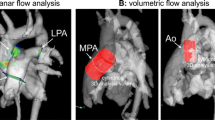

In 2021, a 67-year-old Caucasian woman presented to our outpatient cardiology clinic with worsening exertional breathlessness with no physical stigmata of heart failure. Transthoracic echocardiography (TTE) demonstrated an aortic regurgitation (AR) with a pressure half-time of 597 ms, a vena contracta of 0.45, but visual assessment was graded as moderate to severe AR (Fig. 1a, b, Additional file 1: Video S1). A cardiovascular magnetic resonance (CMR) with four-dimensional flow (4D flow) was done to better quantify the AR and the left ventricular (LV) volumes. CMR was performed on a 3-T Discovery 750w GE system (GE Healthcare, Milwaukee, WI, USA) equipped with an eight-channel cardiac coil. CMR cine images in two-, three-, and four-chamber views were obtained during end-expiratory breath-hold with a balanced steady-state free precession (bSSFP), single-slice breath-hold sequence. Images encompassed the entire heart, aortic valve, and ascending aorta using the following scan parameters: HyperKat acceleration with a factor of 2, field of view 340 mm × 340 mm, acquired voxel size 3 × 3 × 3 mm3, reconstructed voxel size 1.5 × 1.5 × 1.5 mm3, echo time (TE) 3.5 ms, repetition time (TR) 10 ms, flip angle 10°, and 30 cardiac phases. Four-dimensional flow analysis of peak mitral inflow velocity was performed using CAAS MR software (prototype version 5.2; Pie Medical Imaging, Maastricht, the Netherlands).

Mitral inflow assessment of peak early (E-wave) and late (A-wave) inflow velocities. a, b | Transthoracic echocardiography: turbulent aortic regurgitation demonstrated in the apical 2 chamber (a). Pulsed-wave Doppler echocardiography at the tip of the mitral valve leaflet results in very turbulent early filling which prohibited peak mitral inflow E-wave velocity assessment. c, d On 4D flow CMR assessment by peak velocity tracing within the three-dimensional space of the streamlines, the peak velocity during early filling (c) and late filling (d) were recorded by limiting the streamline assessment to length of the mitral valve leaflets. The peak velocity is depicted as the orange ball for mitral inflow and as red ball for aortic regurgitation in the three-chamber view. e, f Both transaortic and transmitral peak velocity traces are presented. Compared with pulse-wave echocardiography, a clearer depiction of peak velocity is seen for both E-wave and A-wave

The LV was not dilated (indexed LV end-diastolic volume 84 ml/m2 and end-systolic volume 26 ml/m2) and had preserved function (ejection fraction 69%). CMR elucidated the AR severity to be mild to moderate (AR fraction 22% with no holo-diastolic reversal in descending aorta). We used novel three-dimensional peak velocity tracing of the transvalvular flow streamlines to investigate whether we could map out the mitral inflow peak diastolic early (E-wave) and late (A-wave) velocities, which were challenging to assess by pulsed-wave Doppler echocardiography (Fig. 1c, d, Additional file 2: Video S2). The flow streamlines can track blood flow from the mitral annulus, and hence there is less chance of picking up the peak velocity of aortic regurgitation flow. Even though diastolic mitral flow is likely to be blunted by the AR, this method allows to at least assess peak velocity through the mitral valve leaflets (Fig. 1e, f). This case highlights that pulsed-wave Doppler echocardiography has a limited role in the assessment of mitral inflow in the presence of AR, limiting its use in LV diastolic and mitral stenosis assessment when AR is present. Secondly, we show for the first time that 4D flow CMR plays a complementary role in teasing out the peak mitral inflow velocities in patients with AR.

Here, 4D flow CMR with valve tracking and automated 3D streamline capabilities allowed better feasibility in the detection of peak mitral inflow velocities by restricting the streamline assessment to the length of the mitral valve leaflets. This capability to manually isolate mitral inflow streamlines during 4D flow mapping is unique to 4D flow CMR [20]. This allowed clearer depiction of E-wave and A-wave transvalvular peak velocities (panel F) by limiting the interference of aortic regurgitant velocities on the acquired mitral velocity measurements. This case illustrates the feasibility of 4D flow CMR in identifying mitral inflow peak velocities and LV diastolic function in patients with aortic regurgitation.

Additional file 2: Video S2. Video demonstrating a 3-chamber view of the heart using 4D flow CMR. Peak velocity was assessed within the three-dimensional space of the streamlines, during early and late filling. The peak velocity is depicted as the orange ball for mitral inflow and as red ball for aortic regurgitation.